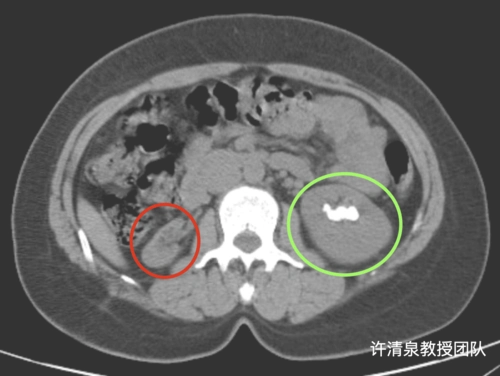

ct影像显示肾脏被巨大结石霸占.长沙晚报通讯员 胡薇华 陈昊 供图

患者ct片显示左右两侧肾结石多发且较大据黄苏宁主任介绍,该患者病情

ct提示钙盐沉着在双肾肾髓质而形成肾钙质沉着,并形成广泛多发结石

ct片上显示肾里塞满了结石